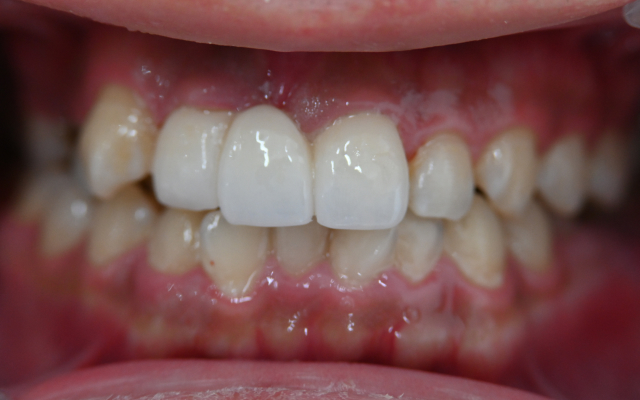

case. 02

ラミネートベニアの症例

before

after

40代 女性 削らないラミネートベニア

施術概要

セラミック治療は形の悪い差し歯や被せ物を治したり、部分的な歯並びの矯正を行うことができる治療です。短期間で歯並びの改善まで実現することが可能です。

金額

66000円(税込)×8本

期間・回数

2週間 / 2回

リスク・副作用

全ての方で、疼痛、咬合痛、冷水痛、抜歯を伴う場合は腫脹や出血などを生じる場合があります。麻酔を行う場合、腫れやむくみを感じる事があります。セラミック・仮歯が欠けたり、外れる事があります。神経の治療や抜歯が必要な場合があります。また、歯並びが変わる事により違和感を生じる可能性があります。